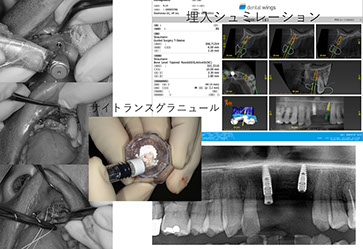

当院のインプラント治療はデジタルCTデータを基に専用ソフトにてインプラント手術をシミュレーションし、手術から最終補綴まで安心、安全そして長期安定性を目指し最新のプロトコルによるデジタルシステムで対応しています。また、骨の状態により骨増生、サイナスリフト、ソケットリフト、ボーンスプレッディング等、様々な対応をいたします。